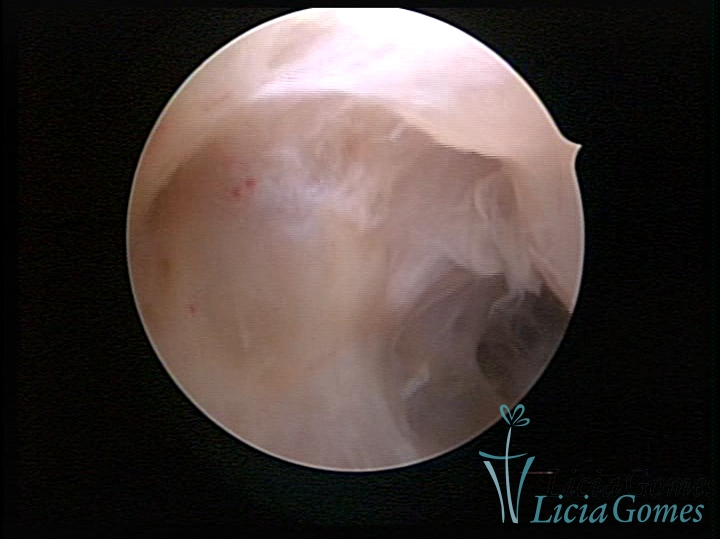

FIBROUS SYNECHIA

Uterine synechiae are scars (adherence) between the surface of the uterine walls, which may occur after the surgical procedure, uterine curettage, or after an inflammatory process in the uterine cavity (endometritis), which may lead to menstrual changes, infertility and obstetric complication such as abortion and premature birth.